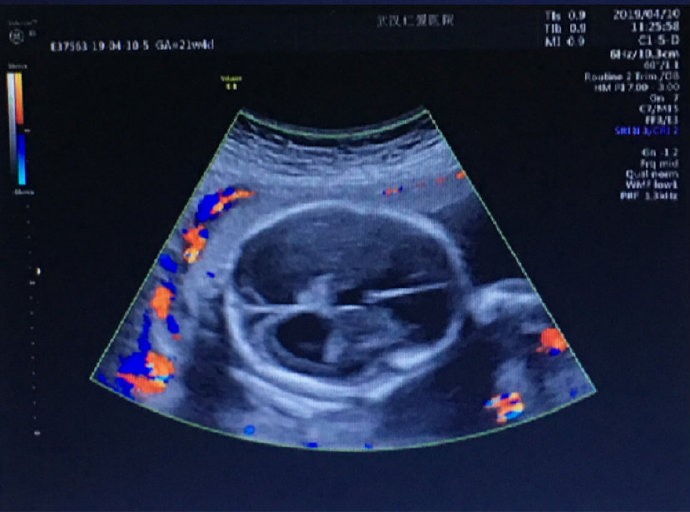

這位孕媽姓劉,家住漢陽,今年24歲,孕22周。前幾日在武漢仁愛醫(yī)院做產(chǎn)檢時(shí),被醫(yī)生告知胎兒重度腦積水。聽到這個(gè)震驚的消息,劉女士內(nèi)心難受不已。

武漢仁愛醫(yī)院超聲影像科王娟主任介紹:“很多初次懷孕,尤其是意外懷孕的女性因?yàn)闆]有懷孕經(jīng)驗(yàn),甚至不會(huì)往懷孕方面去想。當(dāng)她們因?yàn)閼言卸霈F(xiàn)頭痛、體溫升高、犯困、身體乏力、食欲不振等早孕癥狀時(shí)常常會(huì)誤認(rèn)為自己生病了而誤服藥物,這些藥物對胎兒的傷害是特別大的,尤其是在懷孕3個(gè)月之內(nèi),這個(gè)時(shí)期是胎兒發(fā)育最活躍的時(shí)期,必須在醫(yī)生引導(dǎo)下謹(jǐn)慎用藥。”